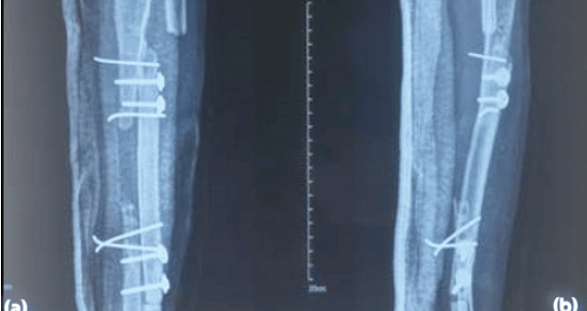

Step 4: Fibular medialization: With the IOM attachments released, the fibula was gently mediatized and aligned with the freshened tibial ends. The fibula was fixed to the proximal and distal tibial segments using multiple cortical screws with washers and K-wires (Fig. 5).

Figure 5: Immediate post-operative X-rays, anteroposterior (a) and lateral (b) views.